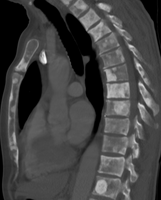

Prostate cancer that has metastasized to the lymph nodes

Prostate cancer that has metastasized to the bone

Most prostate cancers are classified as adenocarcinomas, or glandular cancers, that begin when semen-secreting gland cells mutate into cancer cells. The region of the prostate gland where the adenocarcinoma is most common is the peripheral zone. Initially, small clumps of cancer cells remain within otherwise normal prostate glands, a condition known as carcinoma in situ or prostatic intraepithelial neoplasia (PIN). Although no proof establishes that PIN is a cancer precursor, it is closely associated with cancer. Over time, these cells multiply and spread to the surrounding prostate tissue (the stroma) forming a tumor.

Eventually, the tumor may grow large enough to invade nearby organs such as the seminal vesicles or the rectum, or tumor cells may develop the ability to travel in the bloodstream and lymphatic system.

Prostate cancer is considered a malignant tumor because it can invade other areas of the body. This invasion is called metastasis. Prostate cancer most commonly metastasizes to the bones and lymph nodes, and may invade the rectum, bladder, and lower ureters after local progression. The route of metastasis to bone is thought to be venous, as the prostatic venous plexus draining the prostate connects with the vertebral veins.[63]